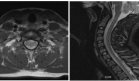

Para evaluar la extensión de la lesión, se realizó una tomografía computarizada contrastada de cuello y senos paranasales, la cual reveló una masa infiltrativa que afectaba la región mandibular izquierda y la fosa pterigopalatina, acompañada de destrucción ósea significativa.

Tres años después de la cirugía inicial, durante una consulta de control de rutina, se identificó una nueva lesión en la región temporal izquierda que se extendía hacia el área parietal, con un diámetro anteroposterior de 7 cm.

Sin embargo, once años después de la cirugía inicial, el paciente presentó una tercera recurrencia con una masa que comprometía el espacio masticador izquierdo, el paladar duro y blando, y un conglomerado ganglionar submandibular. Los estudios imagenológicos mostraron una lesión lobulada de densidad heterogénea que se extendía hacia la base del cráneo y la fosa craneal media, con dimensiones de 36.7 x 53.6 x 42 mm.